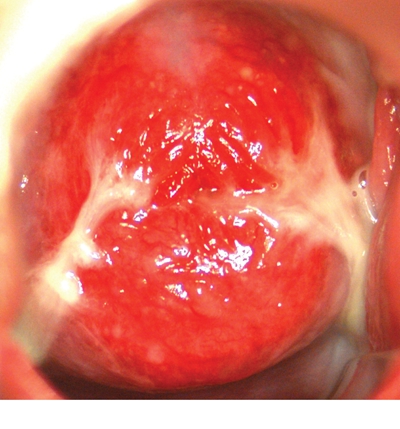

子宮頸癌圖片

宮頸癌

宮頸癌

宮頸癌

宮頸癌

宮頸癌

宮頸癌

宮頸癌

宮頸癌

宮頸癌

宮頸癌

宮頸癌

宮頸癌

宮頸癌

宮頸癌

宮頸癌

宮頸癌

宮頸癌

宮頸癌

宮頸癌

宮頸癌